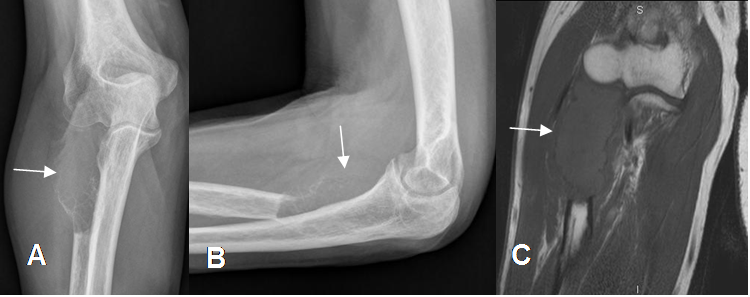

Fig 30. Lesión infiltrante.

A: Lesión destructiva, de comportamiento agresivo.

B y C: Rx AP. Lesión destructiva en el fémur por enfermedad metastásica en A e imagen permeativa en la tibia proximal, por osteosarcoma en B.

Fig 31. Lesión infiltrante.

A: Rx AP, B: Rx lateral y C: RM coronal en T1. Lesión lítica en la cabeza del radio, por metástasis de tumor pulmonar.